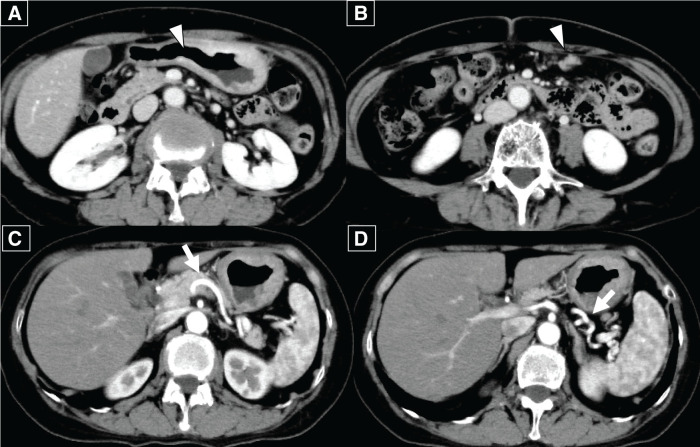

Case presentation: A 65-year-old woman presented with chronic epigastric pain and was diagnosed with gastric cancer through upper gastrointestinal endoscopy. The endoscopy revealed an ulcerated mass at the lesser curvature of the middle gastric body, and a biopsy confirmed a moderately differentiated adenocarcinoma. A laparoscopic distal gastrectomy was initially planned. However, the surgical approach was converted to an open total gastrectomy because of the spread of the tumor to the greater curvature of the gastric body and enlargement of the distal lymph nodes of the splenic artery, which were not included in the planned lymphadenectomy. Postoperatively, the patient experienced no abdominal pain or fever. However, on POD 7, blood tests revealed elevated hepatobiliary enzymes, and a contrast-enhanced CT (CECT) scan showed a loss of flow in the splenic artery and vein, leading to a diagnosis of extensive splenic infarction. A follow-up CECT scan 3 months later revealed a notable reduction of the splenic parenchyma over time.